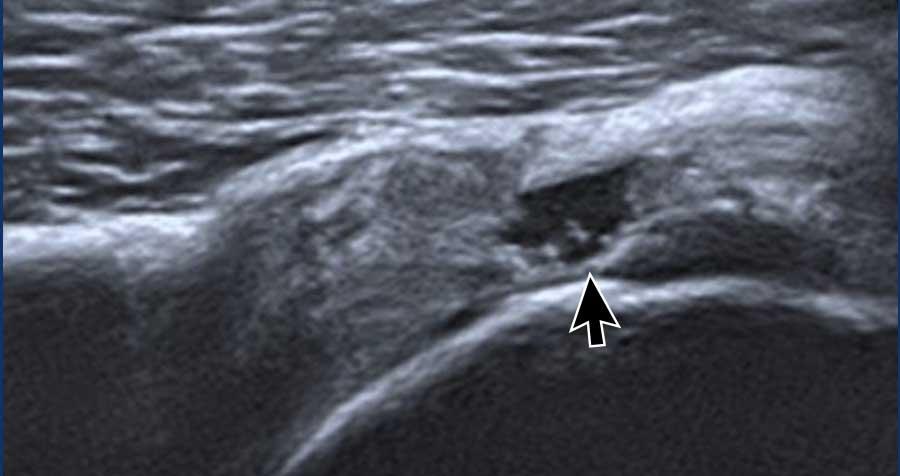

Tính dị hướng

Tính dị hướng là một artefact xảy ra khi chùm tia siêu âm không vuông góc với gân cơ nhị đầu dài (LHB). Sự lệch trục này dẫn đến giảm phản xạ sóng âm, gây mất độ phân giải và làm cho cấu trúc có hình ảnh tối, giảm âm (mũi tên đen). Trong một số trường hợp, điều này có thể tạo ra ấn tượng rằng gân LHB bị trật ra khỏi rãnh liên củ.

Để khắc phục hiện tượng dị hướng, hãy điều chỉnh lại vị trí đầu dò sao cho chùm siêu âm vuông góc với gân. Khi đó, gân cơ nhị đầu dài (LHB) sẽ lấy lại hình ảnh đặc trưng tăng âm, dạng sợi (mũi tên trắng).

Cần lưu ý rằng hiện tượng dị hướng cũng có thể ảnh hưởng đến các cấu trúc khác, chẳng hạn như gân cơ dưới vai trong hình ảnh này, tương tự cũng xuất hiện giảm âm do hiện tượng nhiễu ảnh này.